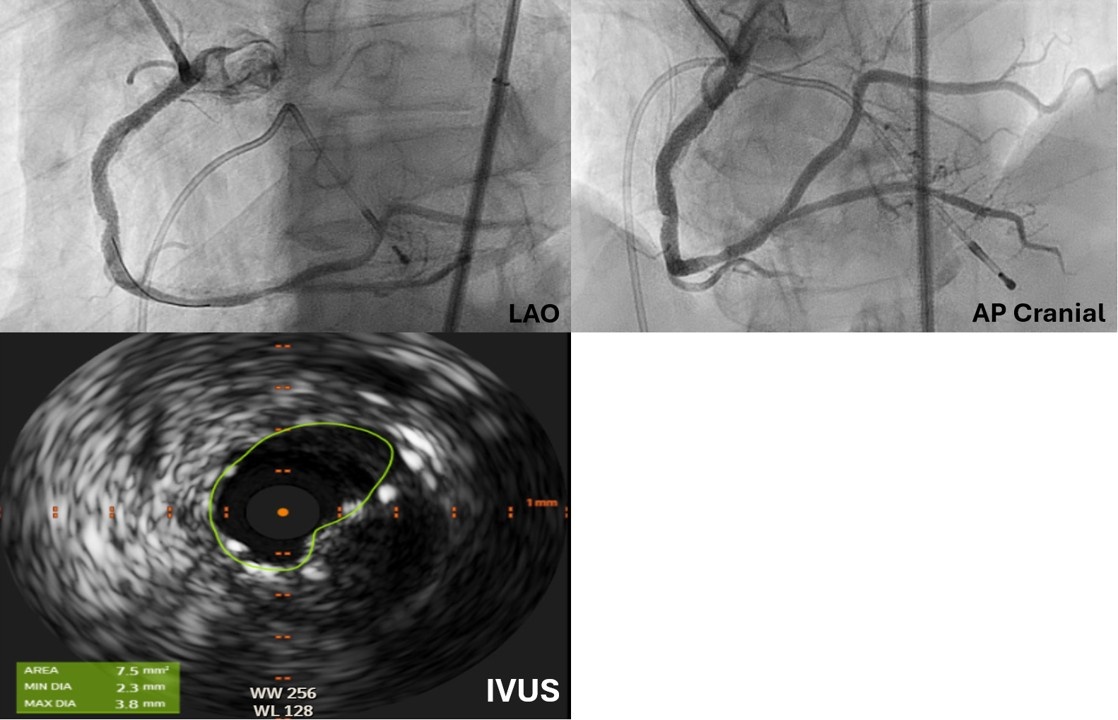

A 65-year-old man presented with unstable angina and calcified right coronary artery (RCA) stenosis (Figure 1) on diagnostic catheterization via radial approach. Percutaneous coronary intervention (PCI) was performed via 7F femoral access using a Judkin’s Right (JR) 4 catheter followed by an Amplatz Left 0.75 guide catheter. Orbital atherectomy (aborted after 6 runs at low-speed because of no-reflow) followed by intravascular lithotripsy (IVL) using a 3.5 mm Shockwave C2+ (Shockwave Medical) was performed. Following this, no equipment could be advanced beyond the mid-RCA calcified nodule (Figure 2).